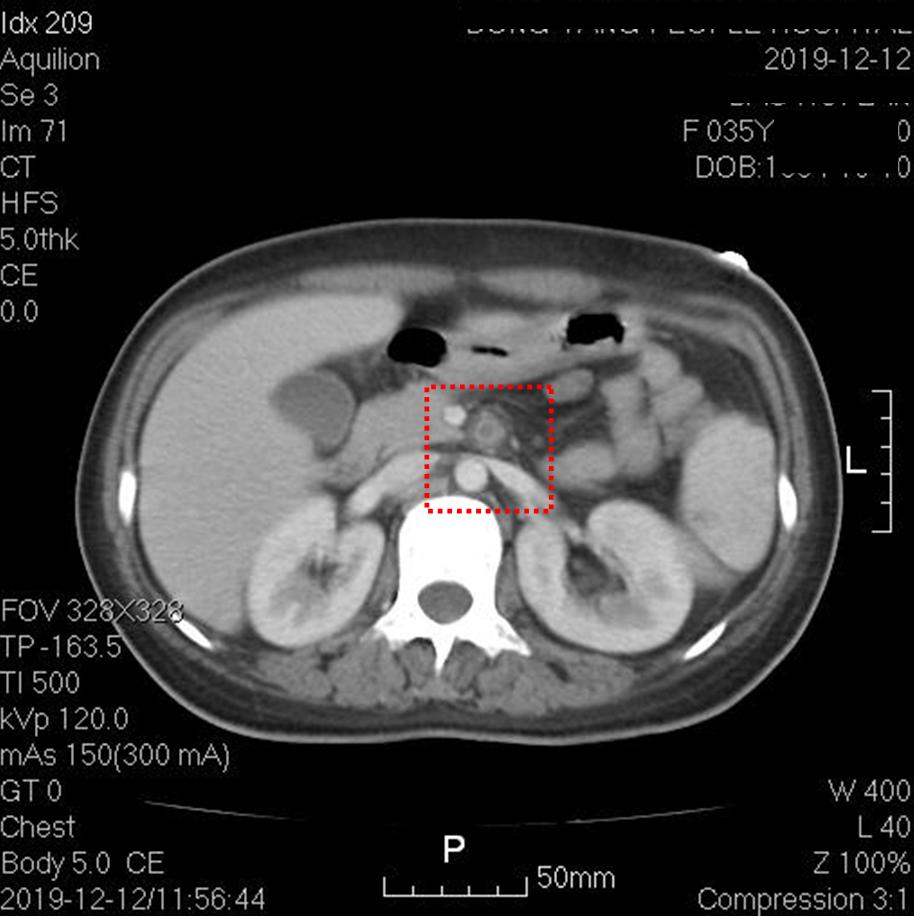

上图红框内为脾梗死。其他层面脾脏还可见数个楔形低密度灶。

上图红框内为左肾梗死。其他层面右肾也可见楔形低密度灶。

上图红框内为肠系膜上动脉根部,可见管腔内未增强,动脉周边组织稍模糊,提示存在炎症改变。其他层面肠系膜上动脉通畅。

上图红框内为右髂总动脉,可见一段长约2.5厘米的管腔闭塞。